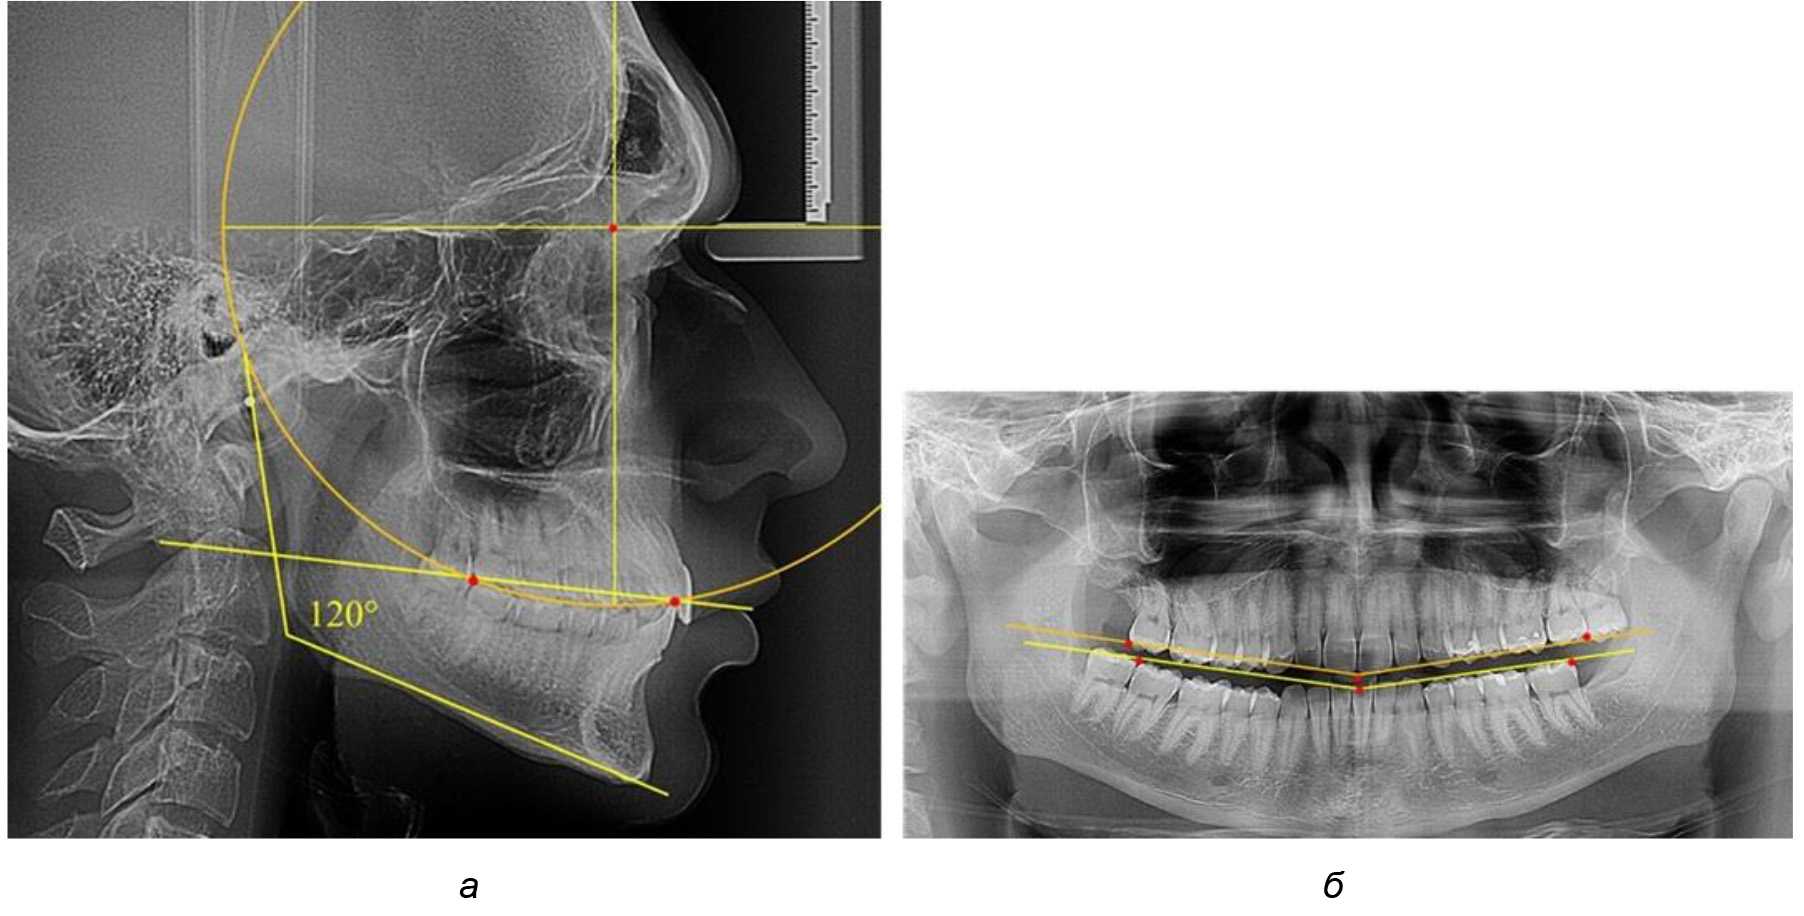

Деление величины радиуса круга к длине окклюзионной линии составило 1,623 ± 0,02. Таким образом, для определения радиуса окружности, соответствующей кривизне окклюзионного контура боковой ТРГ, необходимо измерить расстояние между передней и задней окклюзионными точками и последующим умножением полученной величины на число Фибоначчи (рис. 2).

Рис. 2. Особенности кривой Spee на ТРГ (а) и ОПТГ (б) у людей с признаками вертикального роста

На рентгенограммах людей 2-й подгруппы (30 человек с нейтральным типом роста) величина угла нижней челюсти в среднем составила (120,34 ± 2,19) ° и характеризовала нейтральный тип нижней челюсти.

Глубина кривой Spee в среднем по 2-й подгруппе составил (3,54 ± 0,58) мм, что было незначительно меньше, чем при анализе аналогичного показателя 1-й подгруппы.

Достоверных различий с показателями, полученными при анализе ТРГ и ОПТГ, нами не отмечено (р ˃ 0,05). Деление величины радиуса круга к длине окклюзионной линии составило 1,612 ± 0,02, что, так же как и в 1-й подгруппе, было близким по значению к числу Фибоначчи (1, 618).